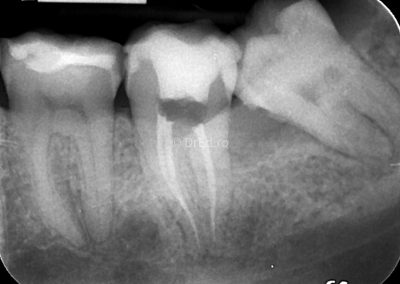

Galerie

Toate imaginile, fotografiile și radiografiile publicate pe acest site sunt protejate prin drepturi de autor și constituie proprietatea exclusivă a Dred.ro.

Aceste materiale sunt furnizate exclusiv în scop informativ și educațional și nu conțin date cu caracter personal sau informații care permit identificarea pacienților, în concordanță cu legislația privind protecția datelor cu caracter personal și GDPR.

Reproducerea, copierea, distribuirea, publicarea, transmiterea, modificarea sau orice altă utilizare, integrală ori parțială, a acestor materiale, în orice formă și prin orice mijloace, fără consimțământul prealabil scris al titularului drepturilor, este strict interzisă și poate atrage răspunderea civilă și/sau penală, în condițiile legii aplicabile privind drepturile de autor și protecția proprietății intelectuale.